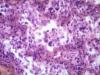

Подскажите как назвать данную пневмонию. По закону парных случаев, на данный момент у меня два разных случая с одинаковой морфологией. В морфологии в альвеолах эозинофильное содержимое, слущенные альвеолоциты, гигантские, многоядерные клетки, выраженный геморрагический компонент, местами немного лейкоцитов, свертки фибрина. Обширные свертки в бронхах. Очень похоже на вирусную, но как ее может назвать морфолог?

Интерстициально-десквамативная.

+ местами похоже на гиалиновые мембраны и в капиллярах межальвеолярных перегородок встречаются мегакариоциты.